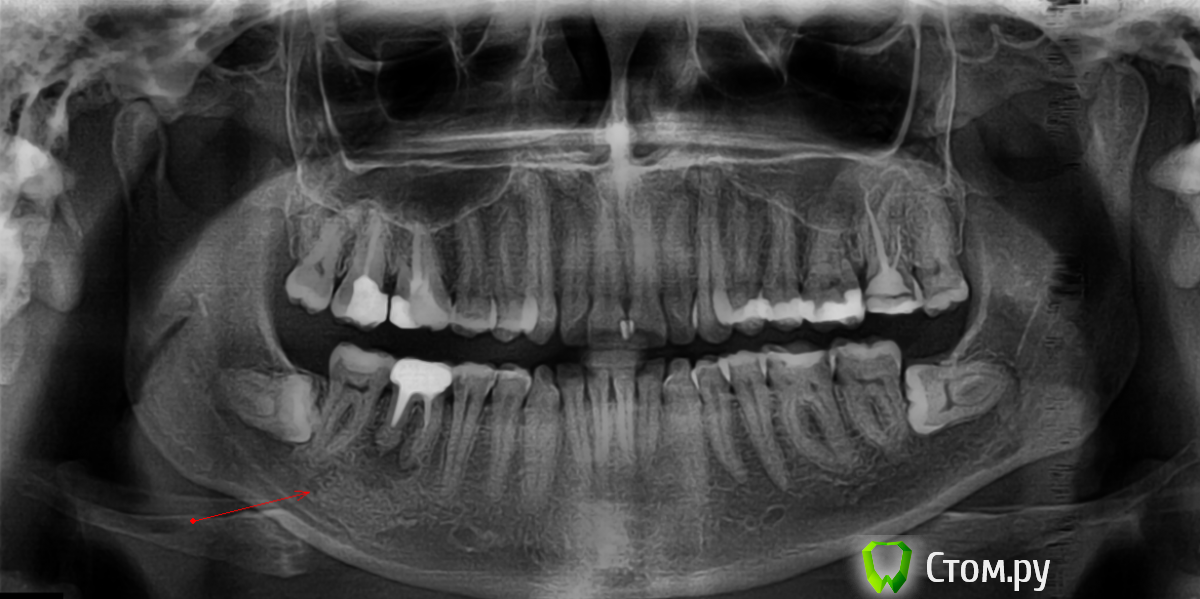

Ann_T Опубликовано 7 июля, 2014 Поделиться Опубликовано 7 июля, 2014 (изменено) Здравствуйте, уважаемые.Прошу Вас высказать свое мнение по том, возможно ли сохранение зуба при наличии такой кисты? и какие методы лечения, по Вашему мнению, будут максимально эффективны в данной ситуации.2 недели назад поставила на зуб коронку (до настоящего времени киста не беспокоила вообще).потом основательно простыла. итог - киста воспалилась.симптомы - сам зуб не болит (в том числе при простукивании).Киста проявляет себя в виде шишкообразного продолговатого уплотнения на десне с правой стороны челюсти (примерное местоположение отразила на рисунке, перепутав стороны. за что извиняюсь))))Проявляется внешне легким отеком на челюсти и ощущается при пальпировании щеки ( и десны). при непосредственном нажатии на эту *шишку* - неприятные ощущения (однако не выраженная боль).С уважением, Анна Изменено 7 июля, 2014 пользователем Ann_T Ссылка на комментарий

sydnik Опубликовано 7 июля, 2014 Поделиться Опубликовано 7 июля, 2014 здравствуйте, а чего скоронкой спешили? для начала надо было каналы пробывать переличить, а уж потом при благоприятном течении, через пару месяцев только протезировать. сейчас пробывать доставать вкладку и переличить тяжкова- то будет, да и очаг большой и время займет много, вообщем я за удаление с послед имплантациейпс зубы мудрости ( к- ые лежат на снимке ) ---- на удаление Ссылка на комментарий

Л Ю С Я Опубликовано 7 июля, 2014 Поделиться Опубликовано 7 июля, 2014 Анна, к сожалению, проблема в зубе. Если не удастся узвлечь культевую вкладку и пере лечить каналы, зуб придется удалять. Воспаление без перелечивания зуба не пройдет Ссылка на комментарий